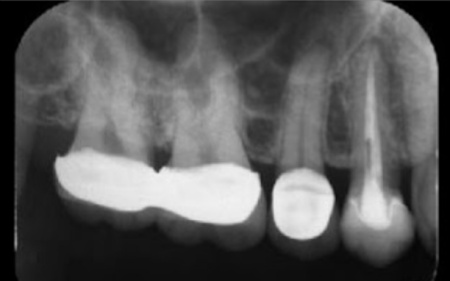

40代女性 炎症を起こした右上奥歯にマイクロスコープを用いた精密根管治療を行った症例

拝見したところ、右上奥歯(第2小臼歯)には保険診療の白い被せ物であるCADCAMが装着されていました。

レントゲン撮影をして検査すると、その手前の右上奥歯(第1小臼歯)には神経や血管が通る根管に清掃と消毒を行う根管治療が施されていました。しかし、歯の内部に細菌が侵入して炎症を起こし、歯根の先に膿が溜まる根尖病巣(こんせんびょうそう)を発症している状態です。

レントゲン撮影で根尖病巣の治癒を確認後、最終的な被せ物を作製するため、歯の形を整えてから型取りを行います。

後日、完成したセラミッククラウンを装着し、噛み合わせや見た目に問題がないかを確認して、治療を終了しました。